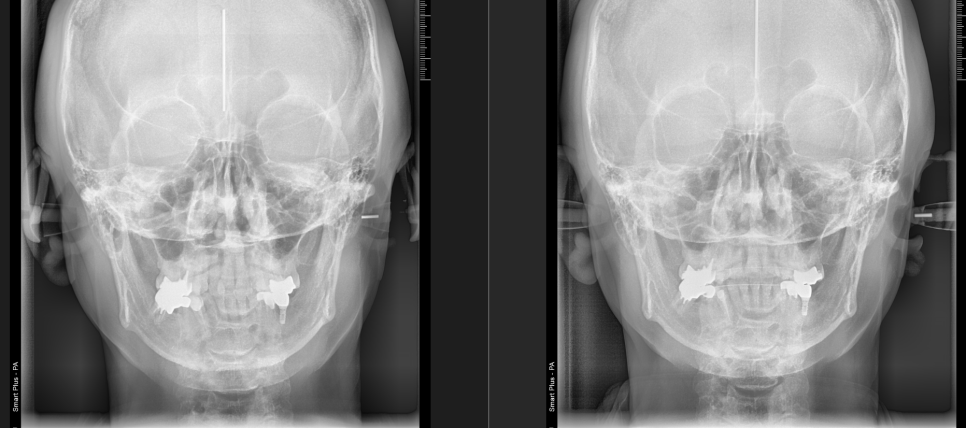

본 환자분은 오른쪽 턱관절이 불편해서 치료를 받은이력이 있고, 교정은 안으로 들어간 치아를 펼치기 위해 하셨습니다. 이런 경우 치아의 비대칭에 의해서 턱관절까지 불편해지고, 얼굴까지 비뚤어졌었습니다. 그런데 역으로 생각해보면 치아교정을 해서 치아를 펴주어서 올바른 위치로 턱관절이 정렬되고 비대칭까지 좋아질수있다는 점을 알 수 있습니다. 왼쪽의 비포에 비해서 오른쪽 이 훨씬 안정된 위치를 보여주고 있음을 알 수 있습니다.